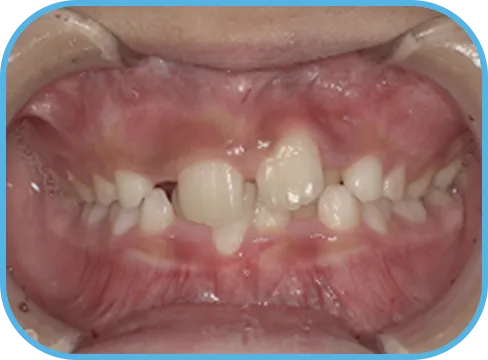

• Before

• 正 面

治療前正面からの歯の様子

• After

治療後正面からの歯の様子

主 訴

前歯が開いている

治療内容

インビザライン・ファースト

治療期間

6か月

治療費(税別)

450,000円+診断料30,000円

リスク・副作用

• 親知らずの影響や加齢などによって、凸凹が生じる可能性があります。

• 治療の初期段階では痛みや不快感が生じやすくなりますが、1週間前後で慣れます。

• 顎の成長発育によって、噛み合わせや歯並びが変化する可能性があります。

• 状況により当初予定した治療計画を変更する可能性があります。